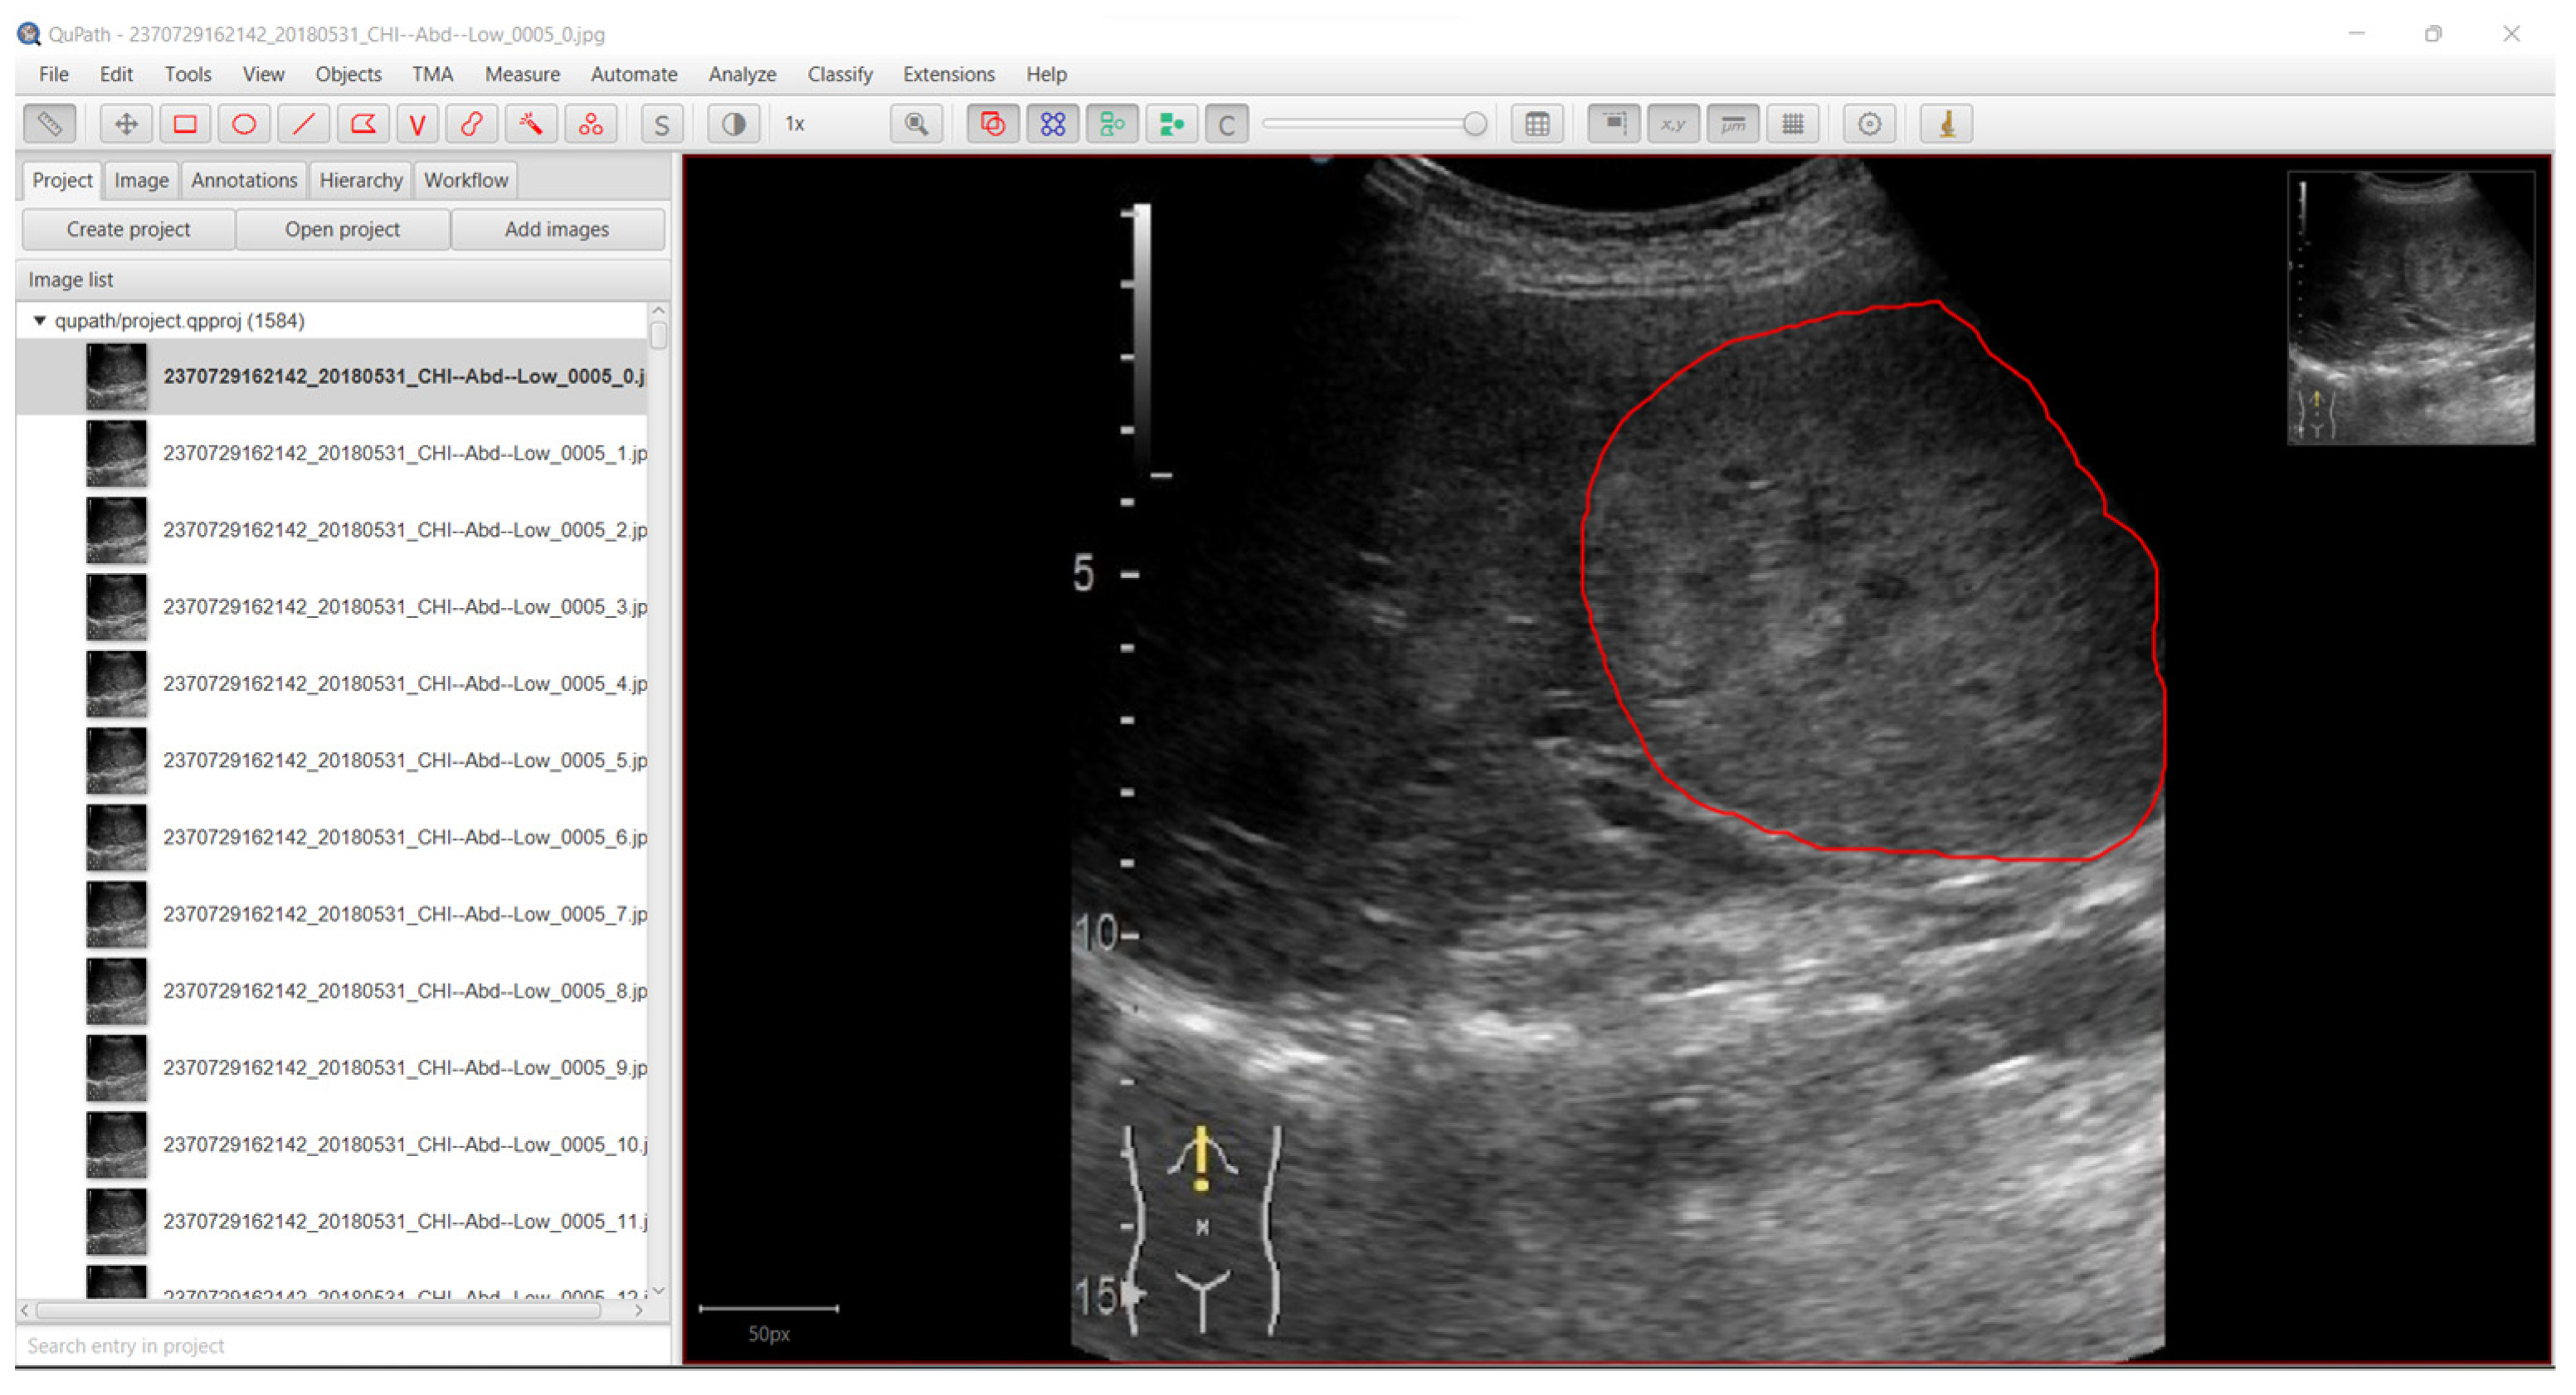

2.1. Data Acquisition

2.2. Data Preprocessing

- Bankhead, P.; Loughrey, M.B.; Fernández, J.A.; Dombrowski, Y.; McArt, D.G.; Dunne, P.D.; McQuaid, S.; Gray, R.T.; Murray, L.J.; Coleman, H.G.; et al. QuPath: Open Source Software for Digital Pathology Image Analysis. Sci. Rep. 2017, 7, 16878. [Google Scholar] [CrossRef]